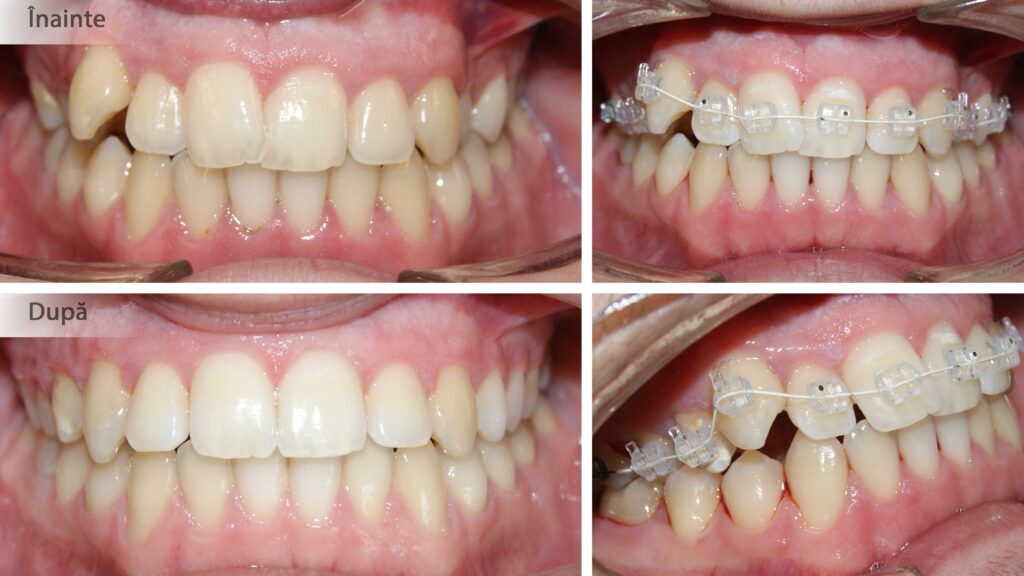

Corectarea angulațiilor dentare și a mușcăturii